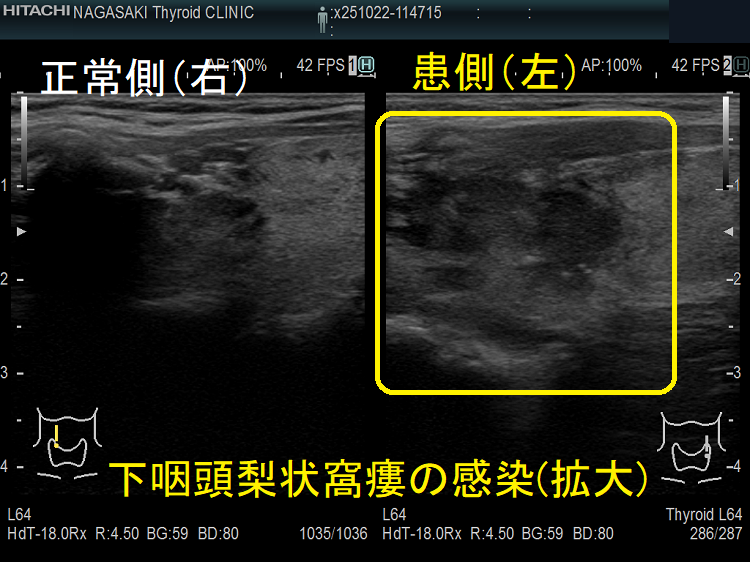

- 超音波検査(エコー検査)で、甲状腺内~甲状腺外の周辺組織に続く境界不明瞭な低エコー領域を認めます。

甲状腺外の低エコー領域があれば、診断は容易ですが、初期は甲状腺内に限局した低エコー領域なので亜急性甲状腺炎との鑑別が難しい。筆者の経験では、どちらの低エコー領域も内部不均一になりますが、亜急性甲状腺炎の低エコー領域は境界不明瞭で飛び石状ですが、急性化膿性甲状腺炎の低エコー領域は単発性・連続性で、比較的境界不明瞭が多い。

①甲状腺内の低エコー領域は片側性が多い(特に下咽頭梨状窩瘻は左側)。甲状腺悪性リンパ腫のような入道雲様の事も。

②甲状腺外の低エコー領域は滲出液・膿瘍で、頭内側に多い

急性化膿性甲状腺炎に至らない下咽頭梨状窩瘻の感染もあります。下咽頭梨状窩瘻が甲状腺内でなく、甲状腺周囲に開口している場合に起こります。